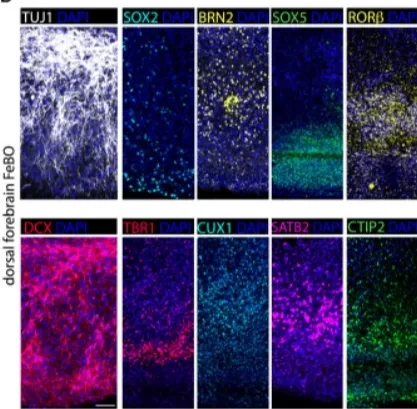

△ 成熟的大脑类器官(扩增2-3个月后成熟)中指示标志物的代表性免疫荧光图像。

△ 四张不同人类胎儿大脑器官的放大图像。不同的神经标记被染色,描绘了它们的细胞异质性和结构。